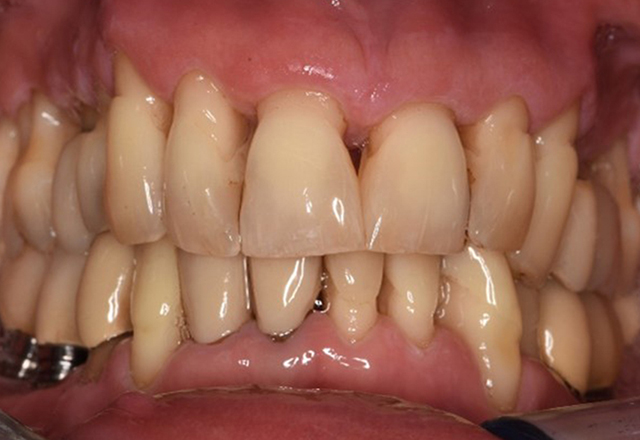

Casi di pazienti secondo l'IPCI seguenti studi di casi servono a mostrare l'interazione tra i fattori di bisogno e di rischio definiti per l'IPC così come gli effetti dei singoli fattori*. La paziente diabetica con una buona igiene oraleUna paziente diabetica di 51 anni con una buona igiene orale si presenta per una seduta di prevenzione. I valori di glicemia sono stabili con HbA1c = 6,2%, per cui si ritiene che la sua condizione possa essere sufficientemente gestita con la metformina (un farmaco per il trattamento del diabete). La paziente non presenta restauri esistenti o precedenti patologie orali. Sulla base dei referti disponibili si può constatare una gengivite nonostante una condizione altrimenti stabile. di più Case presentation: Complex Dental Prosthesis ManagementThe direct relationship between intraoral and general health, as well as the bidirectional influence that they may have on one another, is well-known (1,2). It is absolutely essential to consider both factors when planning preventive intraoral measures and treatment in the dental practice. The primary objective is the maintenance of patient health and quality of life from both dental and medical perspectives. more The (orally) healthy patient with implantsIn the medical history, the 55-year-old patient states that he has no systemic disease and is not taking any medication. The patient’s lifestyle is similarly unremarkable. The patient has a few tooth restorations and two implants (2nd and 4th quadrants). On the basis of current findings, gingivitis is identified in an otherwise stable periodontal condition on the reduced periodontium (stage III, grade A). more The healthy patient with pre-existing periodontal disease & peri-implantitisA 52-year-old patient presents at a preventive care session. The patient has no systemic disease and is not taking any medication. He has had various dental treatments and also has two active carious lesions. In addition, the patient has four implants (2nd, 3rd and 4th quadrants). He is revealed to have early periodontal disease (stage IV, grade B). His periodontal condition is stable; a probing depth of Probing depths (ST) of 5 mm is only evident at the implant in region 36. Gingivitis is also identified. more The Diabetic Patient with Pre-Existing PeriodontitisThis case report of a 52-year-old male with type 2 diabetes and periodontitis emphasizes personalized preventive measures and periodontal health maintenance to manage the moderate disease progression risk. more The 28-Year-Old Cigarette Smoker with Dental Erosions28-year-old patient, smoker, with erosions. The bidirectional relationship between oral and general medical health is very well known. It is no longer sufficient – and arguably even old-fashioned – to consider intraoral conditions in isolation. In order to create a personalized, case-specific preventive and patient profile, it is essential to take a detailed medical history and perform diligent examination of the general medical and intraoral health, as well as considering the two in combination. more Il paziente affetto da endocardite con lesioni cariose attiveIl paziente ha 39 anni e in passato è stato sottoposto ad un intervento per la sostituzione della valvola aortica dovuta a insufficienza valvolare ed endocardite. Assume regolarmente l'ASS 100 come anticoagulante. Per quel che riguarda lo stile di vita, il regime alimentare seguito dal paziente è classificato come “dieta che favorisce la formazione della carie”, per via del consumo regolare di cibi ad alto contenuto di zuccheri e dei sei-sette pasti consumati al giorno. La salute orale del paziente indica un rischio moderato di carie, con lesioni attive. Il rischio di parodontite è basso, tuttavia il paziente è affetto da gengivite. Si formulano quindi i seguenti consigli per il trattamento di profilassi. di più Il paziente trapiantato con iperplasia gengivaleSi presenta un paziente di 71 anni che ha subito un trapianto di reni e con anamnesi di ipertonia (ipertensione). Considerata la sua storia clinica, serve una terapia a lungo termine con ciclosporina che ha un effetto immunosoppressivo e amlodipina che è specifica contro l'ipertensione. Il paziente riporta anche gengive sensibili e sanguinanti. Per quanto riguarda invece lo stato di salute orale, il paziente ha un restauro, presenta un'iperplasia gengivale marcata, una parodontite allo stadio II, grado B con tasche attive e un'iniziale carie radicolare al dente 22 e in più mancano otto denti. Dalla valutazione del rischio di carie si evince un rischio moderato di carie (API 60). Per la seduta di profilassi si possono formulare i seguenti consigli per il trattamento. di più La paziente sana con precedente patologia parodontaleQuesta paziente di 68 anni non presenta alcuna patologia precedente né segue alcuna terapia che possano ritenersi rilevanti dal punto di vista odontoiatrico, e il suo stile di vita non comporta alcun rischio particolare. La paziente ha due impianti (3° quadrante, da cinque anni) e una precedente patologia parodontale (parodontite allo stadio IV, grado B) con perdita del dente. Al momento le condizioni parodontali sono stabili, tuttavia la parodontite aumenta in misura significativa le complicazioni biologiche degli impianti e c'è dunque il rischio di perdita dell'impianto (21). Per la seduta di profilassi si possono formulare quattro consigli. di più